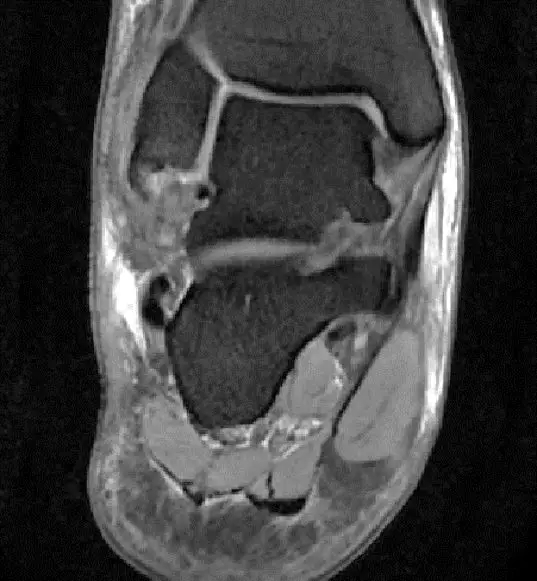

此片可以看到距腓前韧带和跟绯韧带有高信号大片的渗出病变,韧带结构松弛,增粗,这个地方可以看到腓骨前韧带的segond骨折块,所以考虑是踝关节外侧副韧带损伤,腓骨腱的segond骨折。